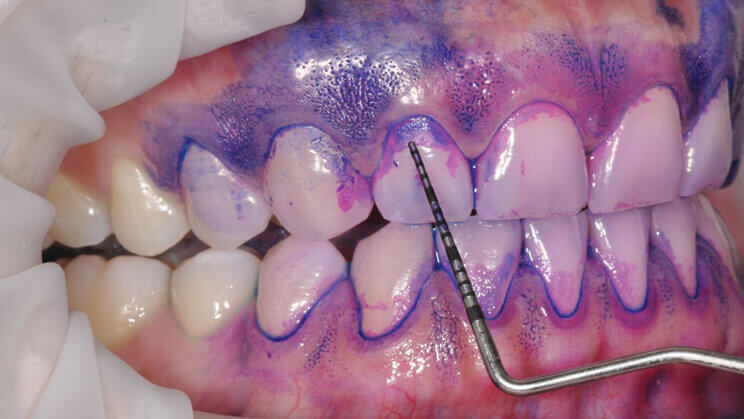

STEP.2 / 染出し

バイオフィルムを染出して見えるようにします

バイオフィルムを染出して患者さんにも見ていただきます。紫~青色に染まったバイオフィルムは36時間以内に生成されたもので、ピンク色に染まった部分は1日以内に生成されたものです。色のついた部分を全て除去することが、バイオフィルムの確実な除去の目安になります。染まっている部分は歯磨きが不十分な個所であると共に、歯周ポケットが深くなる危険のある場所でもあります。